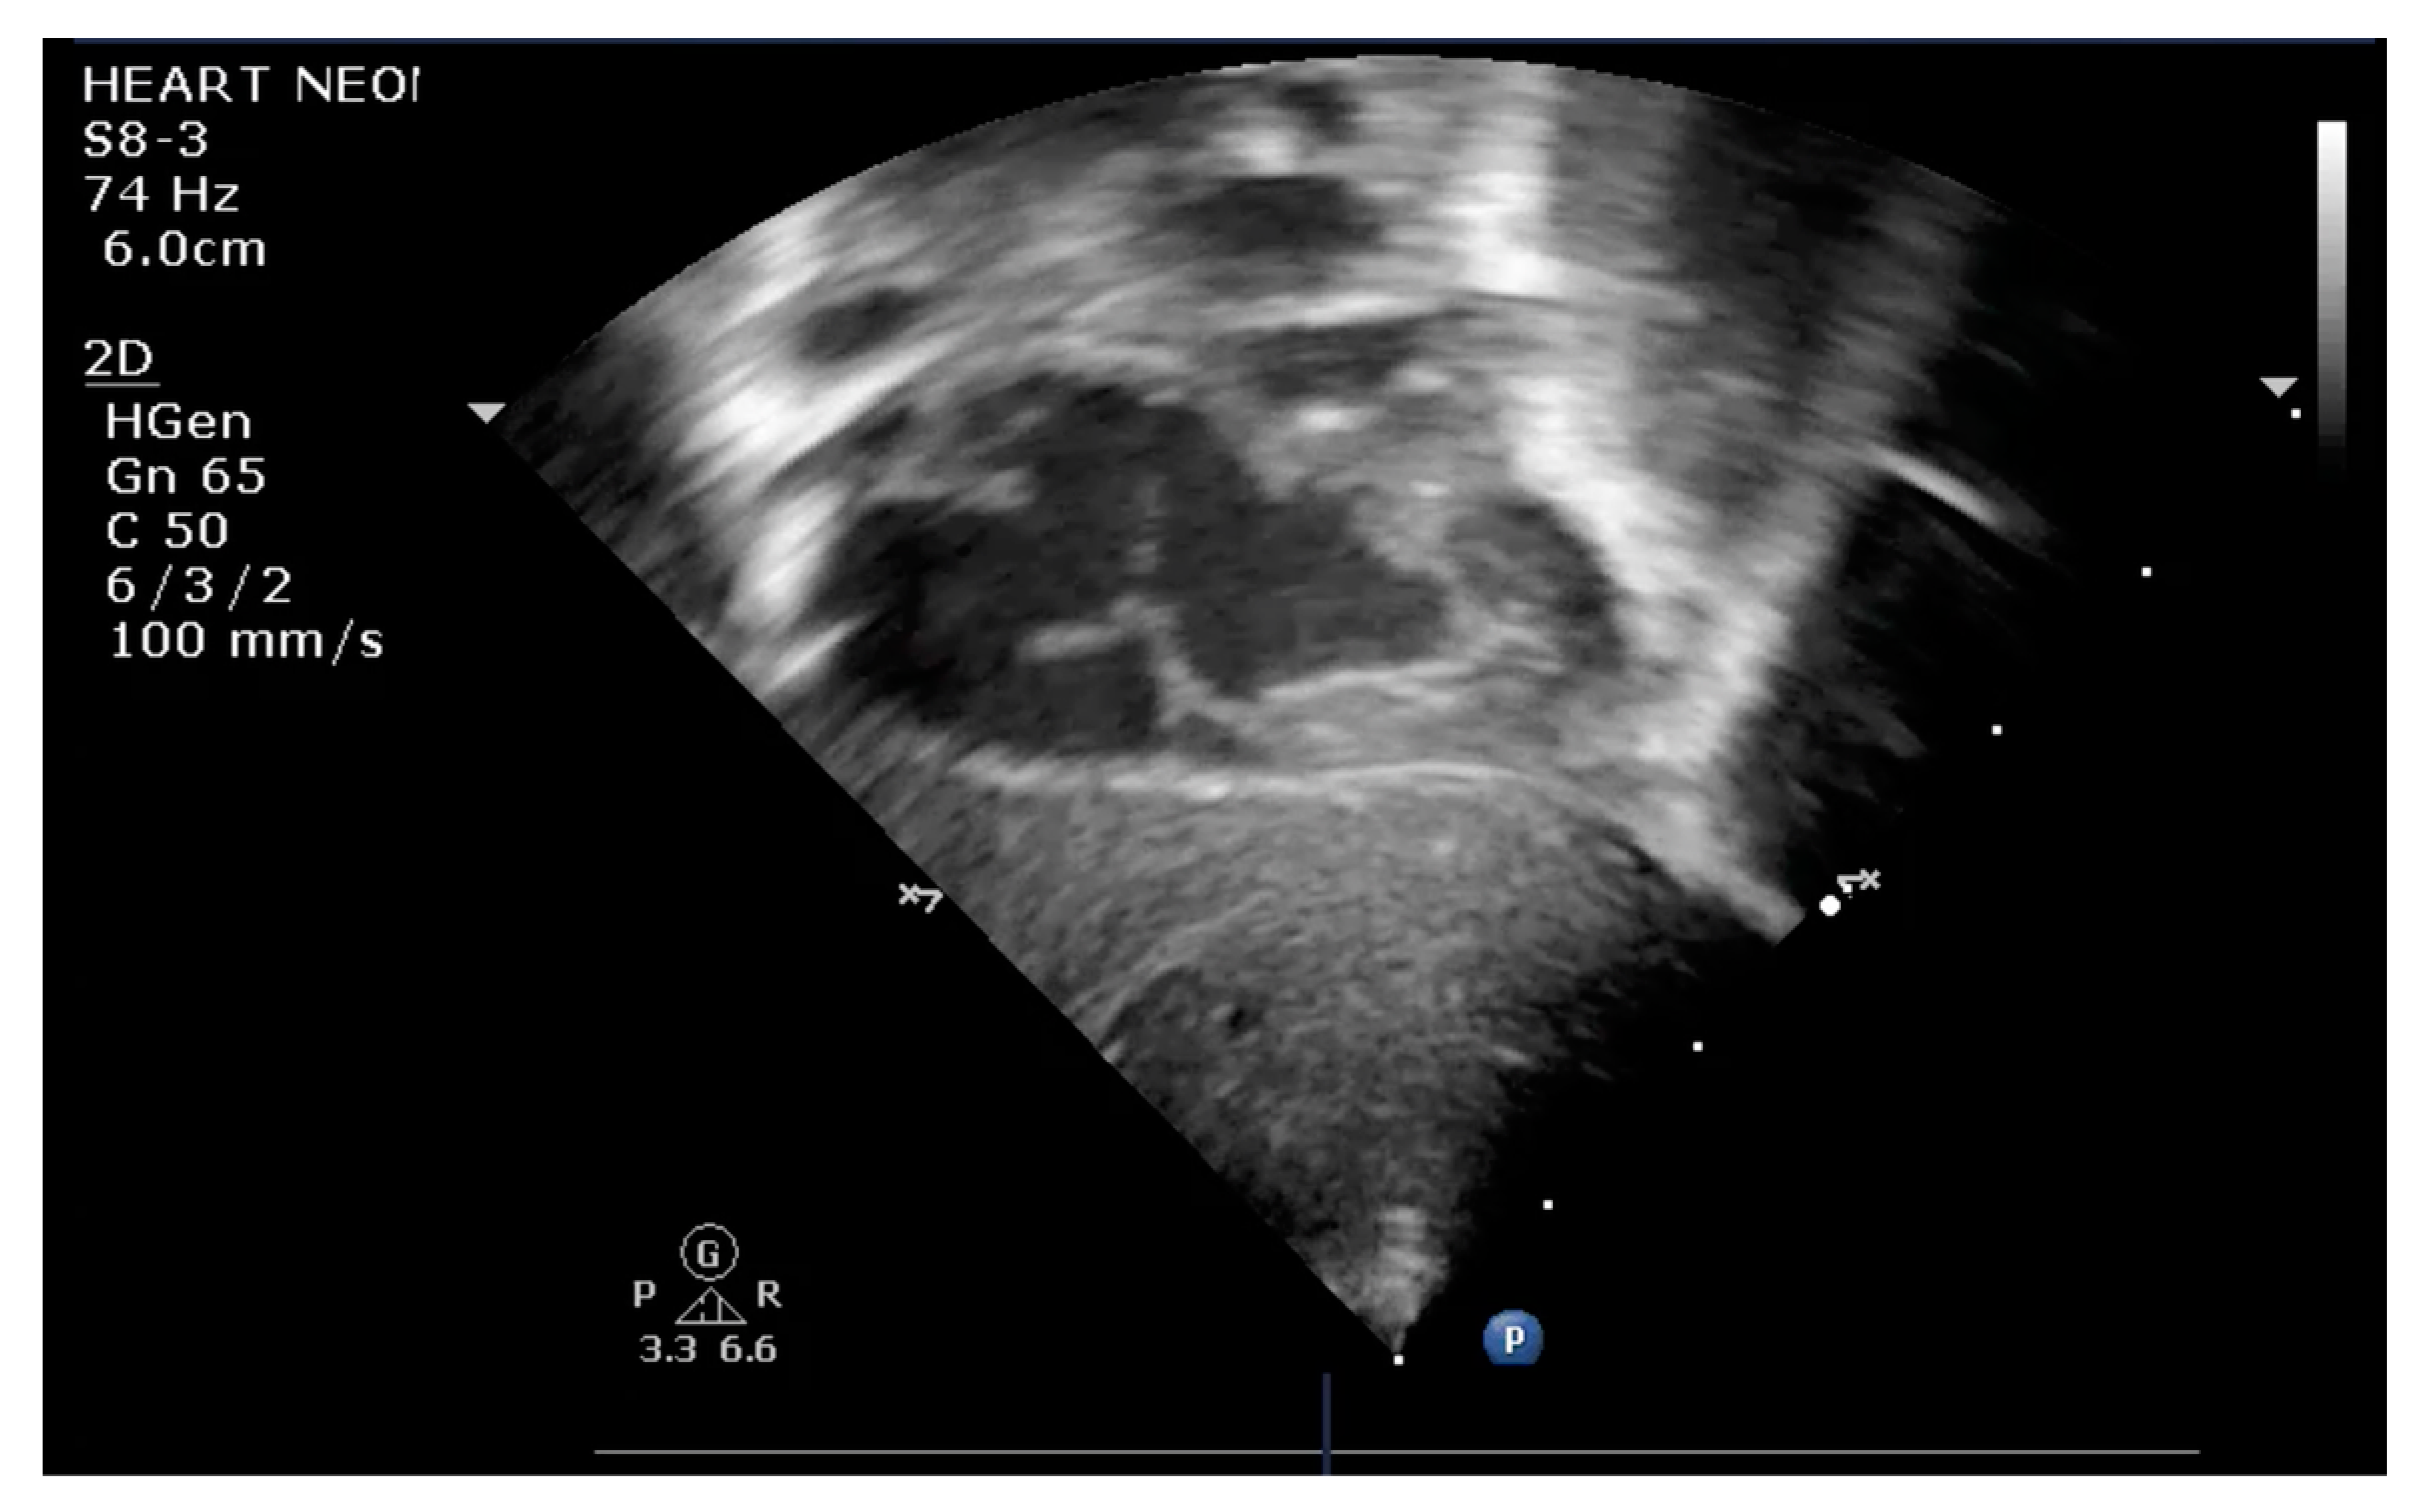

The indication for balloon atrial septostomy was made based on clinical status (low systemic arterial oxygen saturation) correlated with tissue hypoxia (persistently elevated lactate level), echocardiographic assessment (patency and size of interatrial septal defect, ductus arteriosus, and interventricular septal defect), and anticipated delay to surgery. The procedure was performed according to the institutional protocol, at the patient’s bedside, under general anesthesia, and using the Rashkind pull-back technique under echocardiographic guidance (Figure 1 and Figure 2). Vascular access was obtained via a sterile technique via the femoral or umbilical vein. The procedure was repeated several times until satisfactory atrial communication was obtained. The success of BAS was clinically objectified by increasing systemic arterial saturation by at least 10% and echocardiographically objectified by increasing interatrial communication (Figure 3).

Figure 2.

Transthoracic echocardiography subcostal view: inflated balloon in the LA.